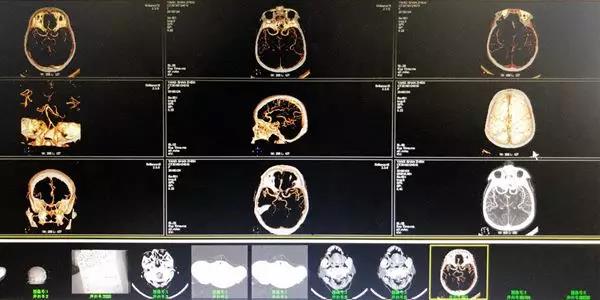

杨奶奶今年76岁,是一位南湖村民。她在入院3小时前突然出现言语不清,左侧手脚无法动弹,到我院急诊已经叫不醒。从她家人口中得知,患者有高血压病史多年,平日并不按时吃降压药,也很少关注自己的血压,入院时测血为177/97mmHg,相当高!我院脑外科李伯炜医师经过评估,诊断患者为缺血中风病,也就是急性脑梗死,并且还伴有高血压和心房颤动。当时,患者情况危急,但由于送医及时,发病在3小时内,我们考虑立刻为患者做静脉溶栓治疗!经过医护的共同努力,现在患者预后良好,神志清楚。

静脉溶栓后复查cta,血管显示清晰。

在这位患者的抢救中,很关键的一点就在于:我们抓住了发病3小时的时间窗!及时诊断,立即静脉溶栓,大大改善了患者预后。